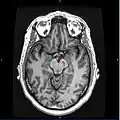

![]() مقطع خلال الأُكيمَة العلوية يبين المادة السوداء. مقطع خلال الأُكيمَة العلوية يبين المادة السوداء. | |